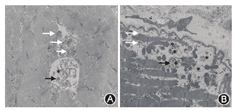

患者男性,15岁,因"发热伴头晕6 d"于2014年5月18日来我院就诊。患者于入院前6 d无明显诱因出现发热,体温最高达38.5 ℃,伴咳嗽咳痰,头晕,乏力,恶心呕吐,呕吐物为胃内容物,无胸痛、胸闷,无肩背部放射痛,无头痛,无意识丧失,就诊于当地医院,给予抗感染、抑酸等治疗,体温恢复正常,仍间断出现头晕、恶心呕吐。遂来我院就诊。患者自幼体弱,易感冒,体力较正常同龄者差,活动后易出现心悸、乏力、气喘,读书成绩不及格。入院时体检:智力低,发育差,身高160 cm,体重42 kg。双肺呼吸音粗,未闻及干、湿性啰音,心律齐,各瓣膜听诊区未闻及杂音,肝于肋下4 cm、剑突下5 cm可触及,脾肋下未触及。双上肢近端肌力Ⅴ级,双下肢近端肌力Ⅳ+级,远端肌力Ⅴ级。四肢腱反射减弱,病理征阴性。家族史:父母及姐姐体健,家族中其他成员无类似疾病。入院后主要生化检查:肌酸激酶2 626 U/L(正常值38~174 U/L),肌红蛋白1453 ng/ml(正常值0~85 ng/ml),肌酸激酶同工酶62.3U/L(正常值0~24.0 U/L),乳酸脱氢酶1 718 U/L(正常值120~300 U/L), ALT 1 043 U/L(正常值9~50 U/L),AST 882 U/L(正常值15~40 U/L)。抗核抗体、抗U1核糖核蛋白、抗Sm、抗SSA、抗SSB、抗Scl-70、抗Jo-1、抗r核糖核蛋白、抗双链DNA抗体均为阴性。类风湿因子、抗链球菌溶血素O、抗环瓜氨酸肽抗体呈阴性。肝炎筛查+戊型肝炎抗体测定结果为阴性。EB病毒、单纯疱疹病毒Ⅰ型及人巨细胞病毒核酸检测阴性。梅毒螺旋体抗体和人类免疫缺陷病毒抗体阴性。红细胞沉降率7 mm/h(正常值<15 mm/h),C反应蛋白13.1 mg/L(正常值0~8.0 mg/L),第三代促甲状腺素、总三碘甲状腺原氨酸、总甲状腺素、游离甲状腺素及游离三碘甲状腺原氨酸水平正常。辅助检查:胸部+全腹CT结果示:(1)全心增大,肺动脉增粗,宽径约3.5 cm;(2)两肺上叶可见多发斑片状密度增高影,以左肺上叶为主,边缘模糊考虑炎症;(3)心包积液,右侧胸腔少量积液;(4)肝脏增大,腹腔积液。心脏超声结果示:(1)室间隔非对称性肥厚(图1A),右心室壁及右心室节制索肥厚(图1B),考虑肥厚性心肌病;(2)二、三尖瓣轻中度关闭不全;(3)左心室正后壁基底段、中段及下壁基底段运动消失;(4)左心室收缩功能减低、舒张功能异常(Ⅲ度,限制性充盈),左心室充盈压增高;(5)右心室收缩功能及整体功能减低;(6)少量心包积液。心电图示:窦性心律,预激综合征图形,心率78次/min,Ⅰ、Ⅱ、Ⅲ、aVF、aVl、V1-6导联ST段压低,T波倒置。24 h动态心电图结果:窦性心律,平均心率为76次/min,最小心率55次/min,最大心率111次/min。室性早搏140个,呈单发、成对及室性心动过速。室上性早搏99个,呈单发、成对及房性心动过速。无心室停搏。ST-T段异常。肌电图示被检双胫前肌、右股三头肌、右三角肌呈肌源性损害。肱二头肌肌肉活体组织检查HE染色可见肌束内结缔组织无明显增生,肌间小血管壁无增厚,未见炎性细胞浸润。部分肌纤维胞质内有典型自噬空泡形成(图2A),胞质内可见不规则形状的嗜碱性物质沉积,肌纤维大小不等,直径20~50 μm,未见肌纤维变性,无核内移增加,未见不透明纤维和环状纤维。改良Gomori三色染色可见空泡样肌纤维(图2B),部分胞质内可见蓝紫色物质沉积。四氮唑还原酶染色和琥珀酸脱氢酶染色可见部分区域氧化酶缺失及中央轴空样肌纤维。非特异性酯酶染色可见空泡区域酶活性增强,部分肌纤维内可见棕黑色物质沉积(图2C)。酸性磷酸酶染色未见明显异常。油红O染色示个别肌纤维脂滴增多。过碘酸希夫染色部分肌纤维内阳性物质不均匀沉积(图2D)。ATP酶染色显示两型肌纤维呈镶嵌排列。免疫组织化学分析提示:肌纤维dystrophin(+),dysferlin(+),sarcoglycan(+)c-dystrophiny和α-sarcoglycan染色可见肌细胞内膜性自噬空泡形成(图2E、图2F)。电镜观察显示肌纤维内出现大量的膜性空泡,部分空泡内存在大量糖原颗粒、溶酶体颗粒以及自噬碎片,空泡周围有散在分布的糖原颗粒(图3A、图3B)。初步考虑为糖原贮积症、Danon病可能。蛋白质印迹证实lamp2蛋白缺失,送检肌肉标本进行LAMP2基因突变检测。检测结果:在LOVD数据库进行检索分析,送检标本LAMP2基因外显子4发现序列异常,c.467_470delTATCinsG,该改变尚无报道,属于移码突变(图4),该位点改变可导致编码氨基酸提前终止,正常人群中无此突变,临床意义明确,证实患者为Danon病。然而由于家属经济以及其他原因,未能进一步对患者基因进行家系验证,明确发病风险。追踪回访患者,令人遗憾的是患者出院仅半个月猝死,患者母亲偶感心悸,无其他不适。